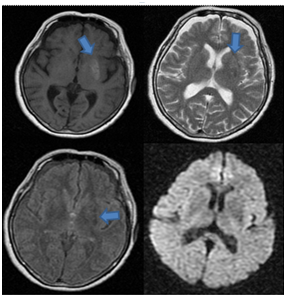

A 68year old woman, without any medical history, consulted for seven days of non-rhythmic involuntary distal movements of sudden onset on the right upper extremity. Also, she presented wide brupt proximal movements, with variable amplitude and frequency. With the passing of the hours the movement compromised the ipsilateral lower extremity limiting the gait. Associated to this sherefered 12kg of weight loss in 2weeks, polyuria and polydipsia. In the physical exam right hemiballism and hemi chorea was present with an additional athetosical component. In the cerebral computed axial tomography no alterations were documented but the cerebral nuclear magnetic resonance shows in the T1 weighted sequence a hyper intensity in the left ventricular nucleus which is Hypointense in the FLAIR and does not generate vasogenic edema or mass effect Figure 1.

Figure 1 Cerebral nuclear magnetic resonance shows in the T1 weighted sequence a hyper intensity in the left lenticular nucleus which is Hypointense in the T2 and FLAIR sequences and does not generate changes in diffusion.

The cerebral computed axial tomography can be normal or demonstrate hyper density in the putamen, in the caudate nucleus or in both, always contra lateral to the hemi chorea. Normally, there is not surrounding edema or mass effect. In the magnetic resonance imaging a hyper tense lesion can be identified in the basal nuclei in the T1 sequence and a variable signal in the T2 and FLAIR.3,13